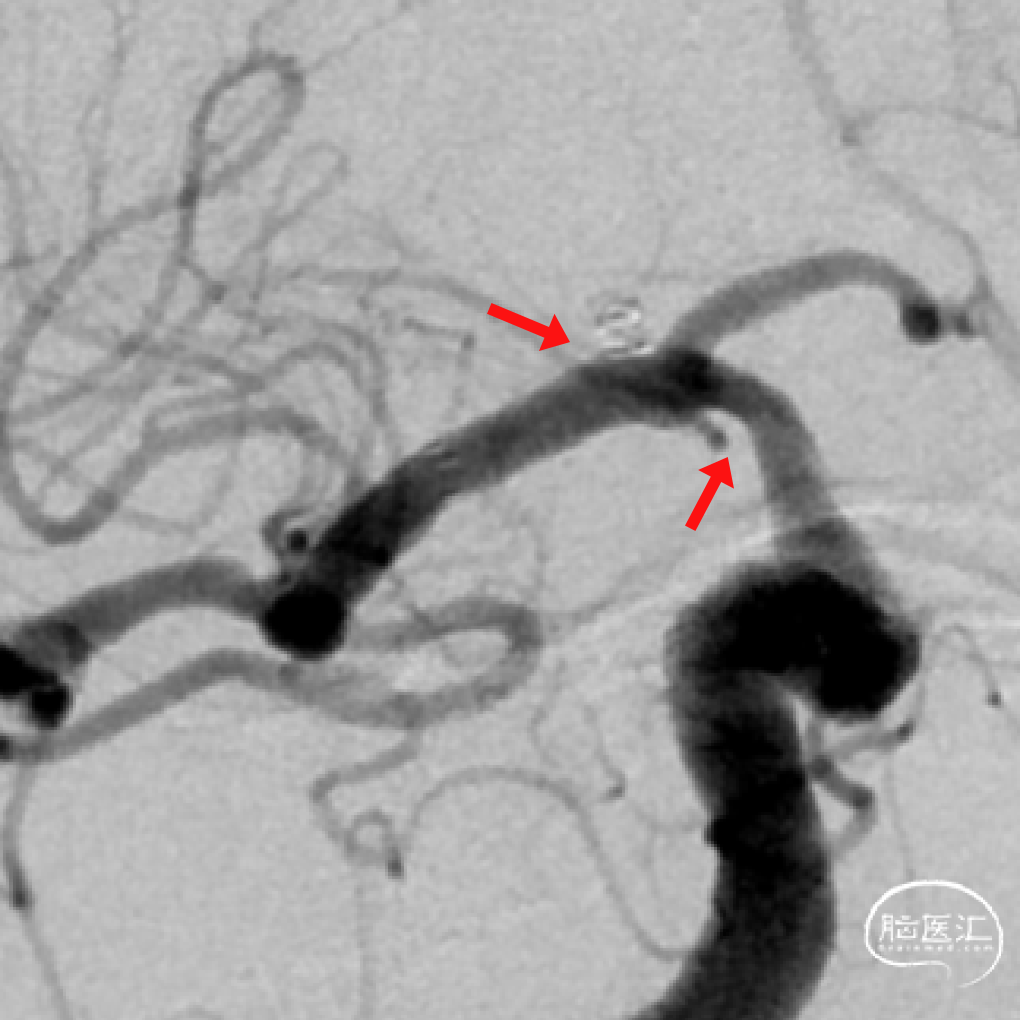

➢DSA(2023.11.10)

头颅MRA:右侧颈内动脉C7段狭窄。

左侧大脑中动脉M1段狭窄、左侧椎动脉狭窄。

右侧颈内动脉C7段狭窄

右侧M1段动脉瘤

左侧大脑中动脉M1段狭窄